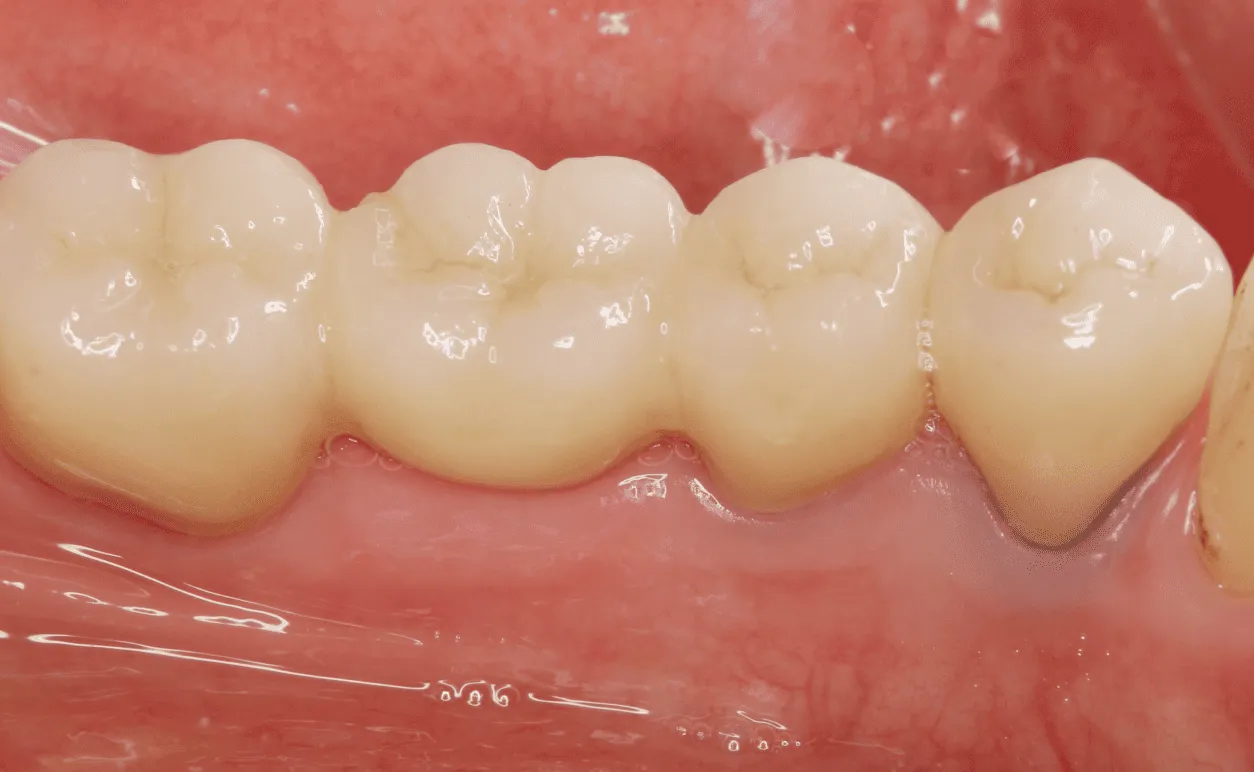

• 自費のむし歯治療

セラミック

セラミックなど、見た目や機能に優れた材料が使えます。審美性にすぐれ、金属アレルギーのリスクもなく、長持ちしやすいのが特徴です。